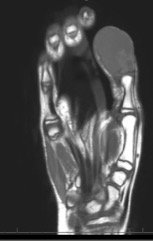

A 12-year-old male presented to the emergency department with right thumb pain and a mass for four months (see images). He denied fevers, chills, change in appetite, or fatigue. He noted that the lesion was growing and “bleeds easily if bumped.” He denied any trauma to the thumb, except “hitting it” months ago while in football practice.

Magnetic resonance imaging (MRI) showed an “expansile, destructive solid and cystic mass with aggressive…characteristics…” (see images). Tissue biopsy confirmed a giant cell tumor arising from the bone. The patient underwent a debulking procedure, and later a distal amputation. Follow-up on pathology showed negative margins.

The best imaging study is MRI, to assess for bony and tissue involvement and surgical approach. Computed tomography may be used; however, it doesn’t delineate the soft tissue and bony connections as well. Standard oncology labs should be drawn as well, including: CBC with differential, LDH, uric acid, CMP, ESR. The growth of the tumor is insidious and therefore imaging should be done based on clinical concern. In the ED setting, if close follow up can be ensured, imaging can be done as an out-patient. Annual surveillance is recommended for at least five years in most patients, even after total resection, according to some studies.3